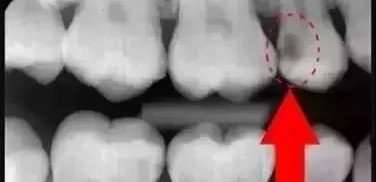

(3)牙髓病以及根尖周病:有利于临床工作中观察根管系统解剖及根尖周骨质情况,发现遗漏根管、评价根管充填的效果等。